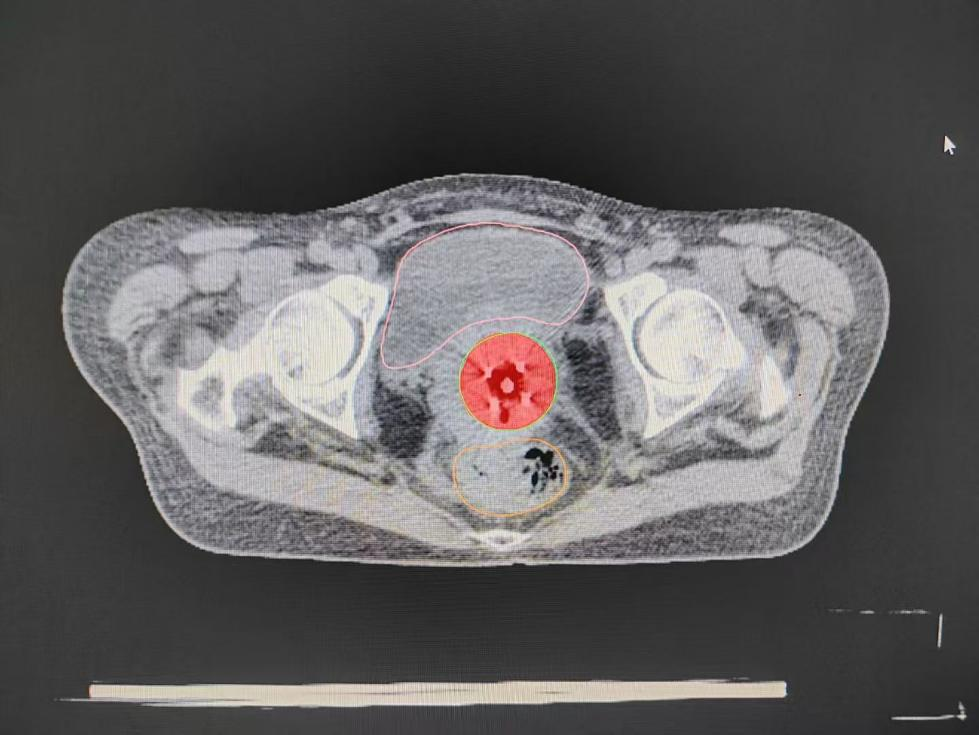

随后,团队争分夺秒护送患者进行CT定位扫描。在影像引导下,精准勾画靶区,制定了个性化的放射治疗计划。最终成功为患者实施了高难度、高精度的急诊后装放射治疗。治疗结束后,患者的阴道出血量显著减少,病情得到有效控制,成功脱离了危险期。看着患者转危为安,参与救治的所有医护人员都松了一口气。